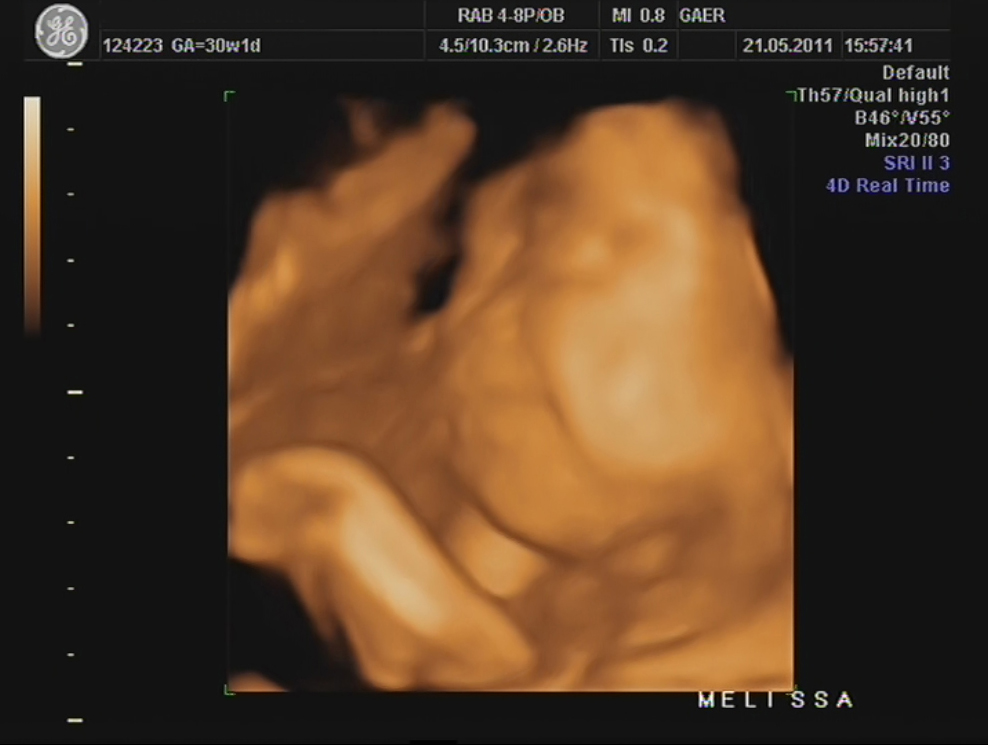

Durante a eco, percebi que a Dra ficou tempo a mais a avaliar o mesmo local e ao fim ela me explicou que viu uma lamina de água a volta do coraçãozinho da minha pricesa.

Ela me explicou que isso acontece a alguns bebés e que não devo me preocupar, que temos que fazer um exame mais detalhado para avaliar o coraçãozinho dela que será feito no Hospital São João e que hoje já trataria de marcar isso...